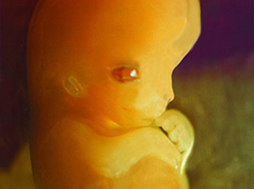

31 srpna-ultrazvuk-Pan doktor našel 2 oplodněná vajíčka,jedno menší,druhé větší.